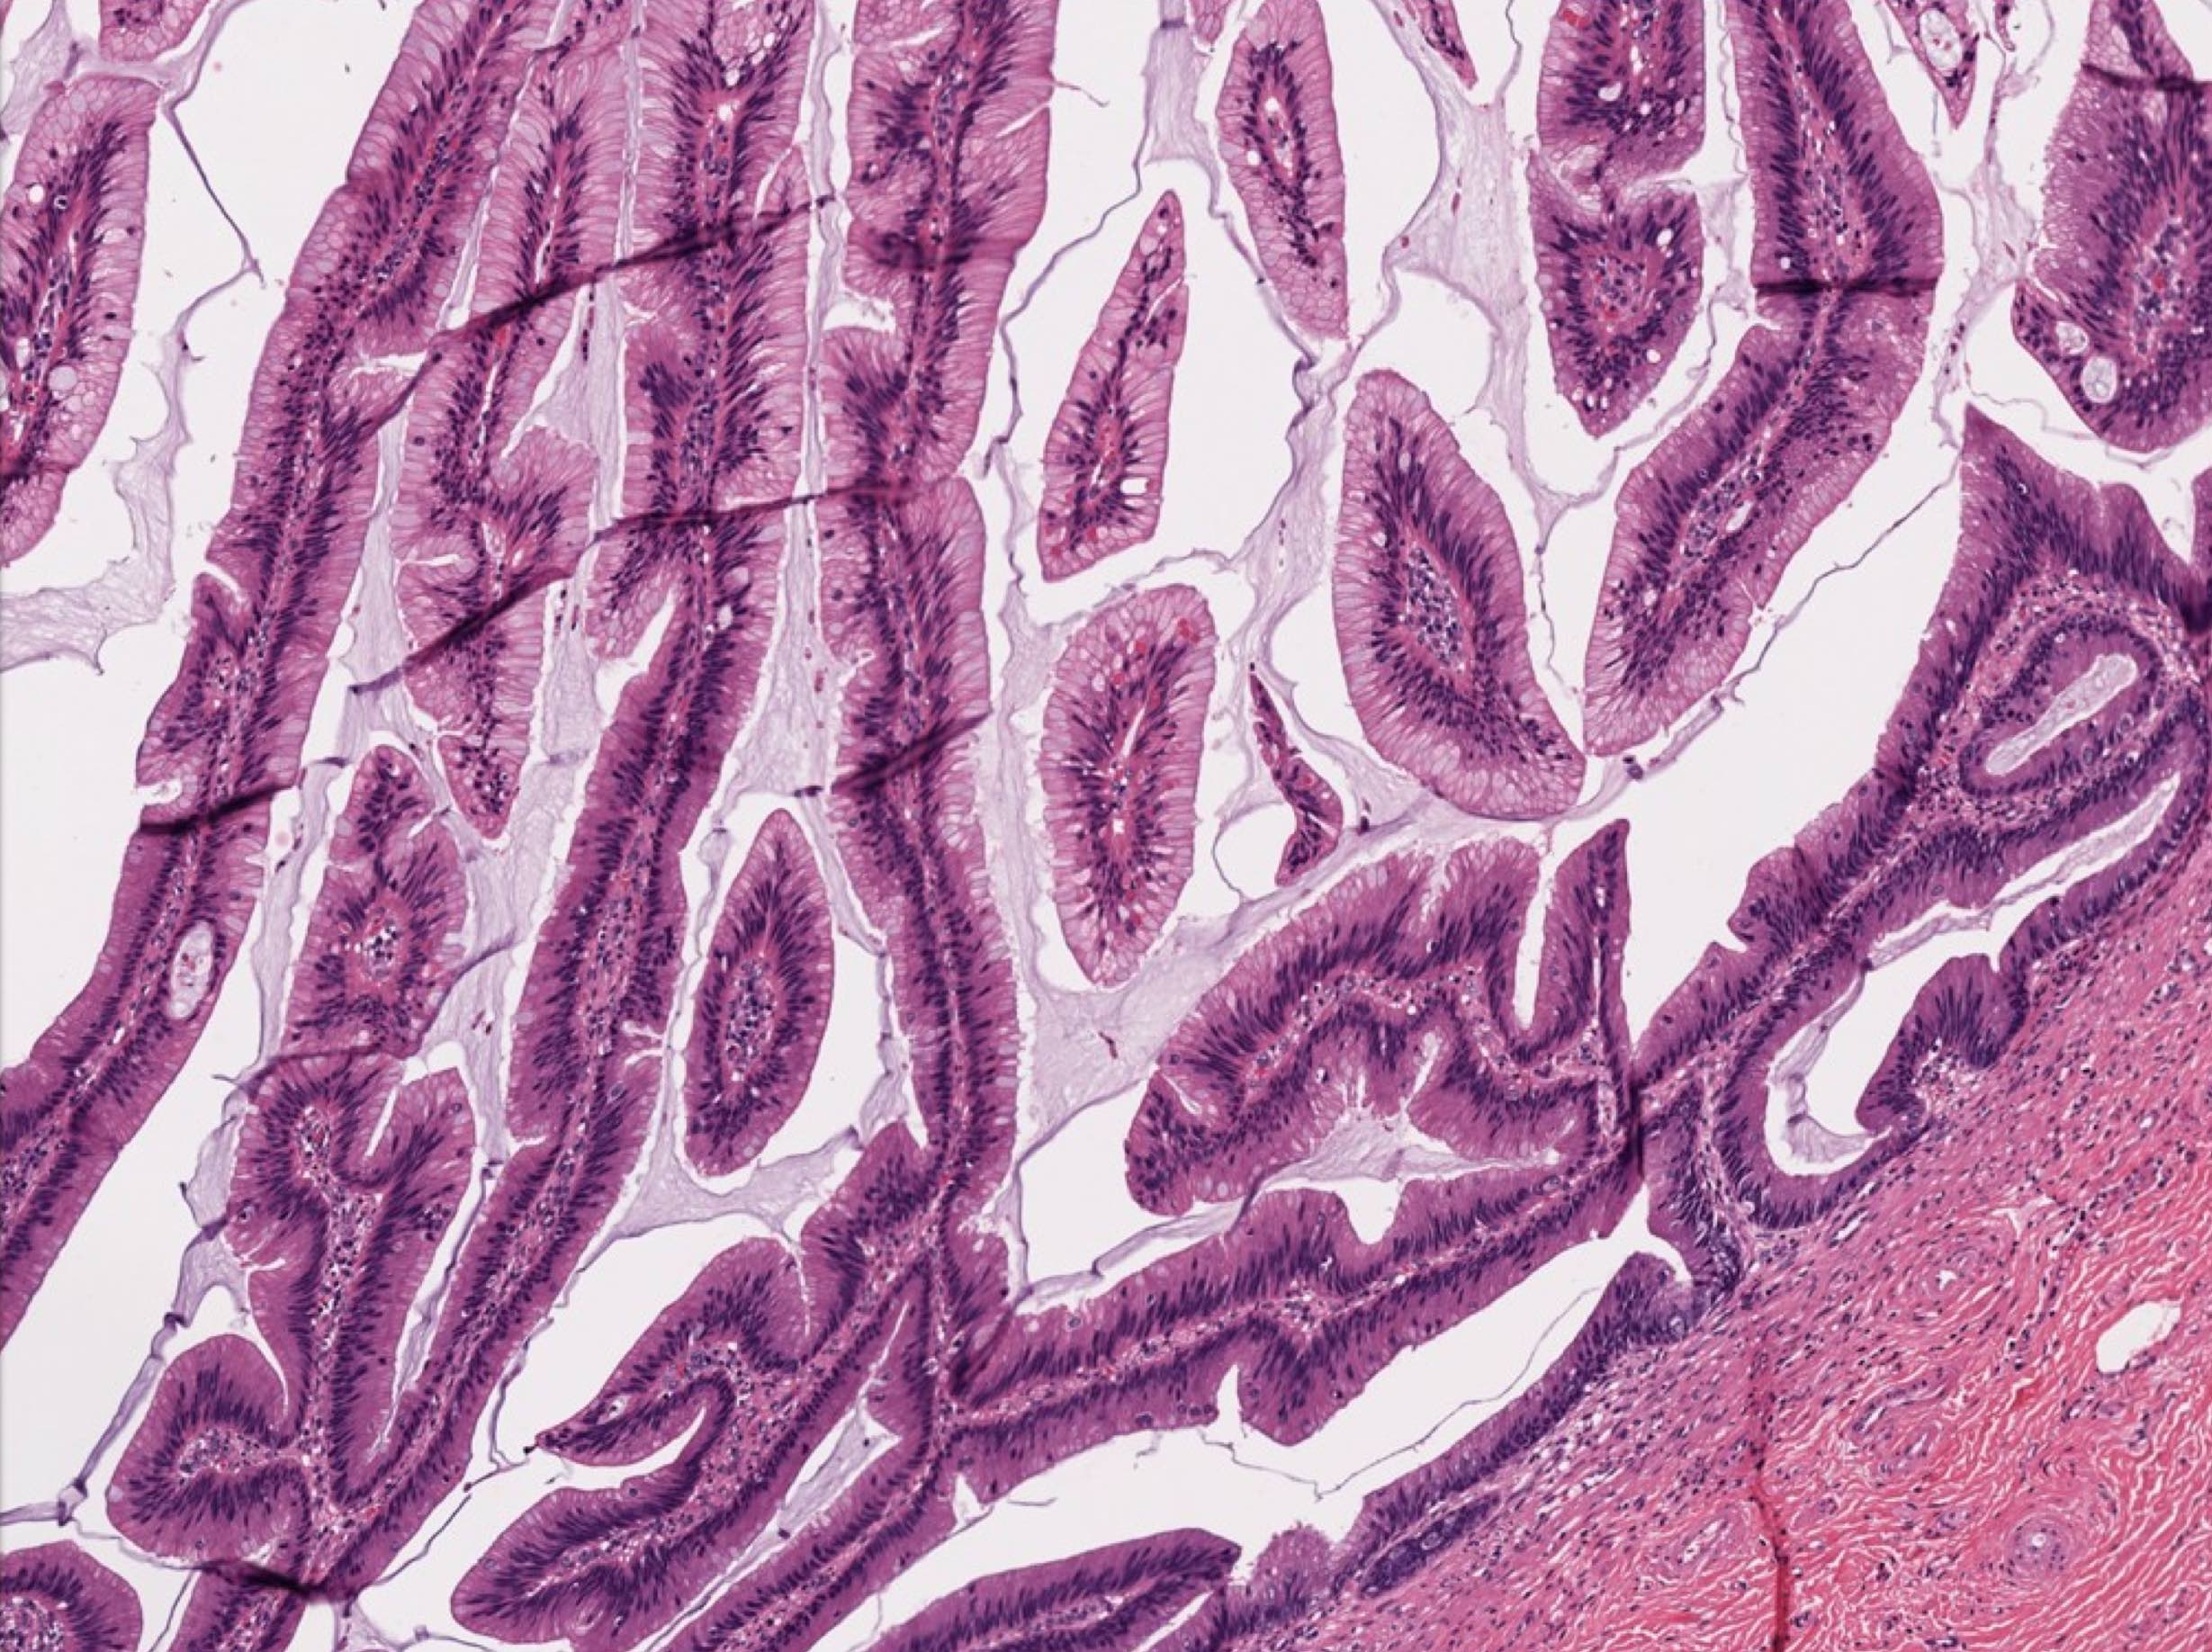

Microscopic (histologic) description

- Villous or occasionally flat proliferation of mucinous epithelial cells originating from appendiceal lumen

- Lesional cells typically demonstrate abundant apical mucin with elongated nuclei and low grade nuclear atypia (LAMN); however, nuclei may appear compressed or rarely high grade (HAMN)

- Often associated with atrophy of underlying lymphoid tissue, crypt loss and effacement of muscularis mucosae

Microscopic (histologic) images

Contributed by Raul S. Gonzalez, M.D. and Michael Feely, D.O.